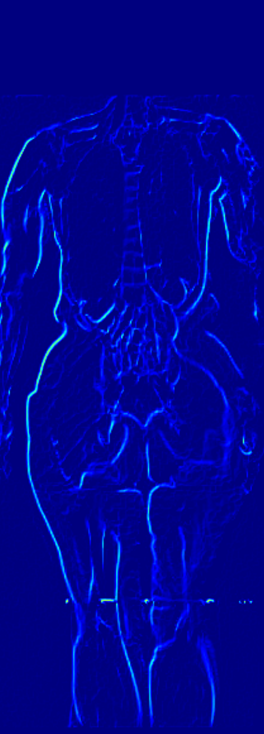

3.4 DXA to MRI Volume Generation

DXA is a single image data modality that is similar to X-ray but includes other non-bony information such as tissue mass [67]. It measures bone mineral density and body fat composition. The radiation level is low enough that it is acceptable for conducting studies of healthy participants, such as the UK Biobank. In order to leverage X-Diffusion to synthesize the MRI volume from a single DXA (as in Figure 3), they have to be aligned, and registered. Note that, the size of the DXA does not match the MRI () and the scans are not registered. The two modalities in UK BioBank were not taken simultaneously but close in time hence why we believe registration is feasible for these two sequences as illustrated extensively in [79].

In order to tackle this domain gap, we leverage a registration network [79] paired with a X-Diffusion to achieve DXA to MRI slice generation. [79] introduced a multi-modal image-matching contrastive framework, that is able to learn correspondences between DXA and middle coronal MRI slices. These networks extrapolate the DXA scan by a transform to the coronal MRI slice by harnessing the embedded patterns and features of the DXA and the coronal MRI mid-slice. X-Diffusion is then trained on the registered DXA () and corresponding MRI slices in () in the target MRI volumes and is able to produce precise MRI volumes that align with the DXA scans (see Figure 5 left). The other details are similar to Section 3.2 and Section 3.3.

Notably, X-Diffusion achieves state-of-the-art dB for a few input slices while baselines require more than 60 input slices to achieve similar performance (Figure 7). The margin is more than 12 dB PSNR for the 1-slice input in both the BRATS and the UK Biobank benchmarks (see Table 1 and Figure 6). For reference, two randomly sampled MRIs from UK Biobank would have a PSNR of 15.95 dB 0.36 (on 4800 randomly sampled examples). Omitting the preprocessing step of alignment DXA to MRI, leads to a drop of PSNR on average by 2.87 dB (29.01 dB 26.14 dB). The slices from 3D reconstructed volumes at varying depths and axis of rotation, visually match the ground truths for both brain and whole-body scans (see Figures 4 and 5 left). We also plot the error map (Figure 3) and the spread of the error (Figure 5 right) of such X-Diffusion generations to highlight the differences with the ground truth MRIs.

Preservation of Spine Curvature. For the spine segmentation on UK Biobank, we use a UNet++ model [83] with Dice Loss. We use a model trained to predict curves on DXA on UK Biobank [11]). We measure the Pearson correlation factor [11] of spine curvature measured on the generated MRIs where the input is a single MRI coronal slice, a single sagittal slice, or from the paired DXA, against the curvature of reference real MRIs of the same samples. The correlation coefficients are 0.89 for the coronal MRIs, 0.88 for the sagittal MRIs, and 0.87 for the DXAs on the test set of 308 human-annotated angles. We can then bin the curvature of the spines under different scoliosis categories based on human-annotated angles: mild: , moderate: , and severe . We show the results in Figure 8. This illustrates that the generated MRIs preserve the spine curvature from normal to severe scoliosis cases. Additional details about spine curvature are provided in supplementary material.

B.4 Preservation of Spine Curvature and Fat

For the spine segmentation on UK Biobank, we use a UNet++ model [83] with Dice Loss. We use a model trained to predict curves on DXA on UK Biobank [11]. We show in Figure IX that generated MRIs preserve the spine curvature from normal to severe scoliosis cases. We also study the case when DXA is used to generate the MRIs and show in Figure IX how the correlation to real curvatures compares to the input MRI case. The curvatures of the MRI generated from the coronal plane match the DXA curvatures more than the curvatures generated from sagittal MRI. This is expected since the antero-posterior plane of DXA is equivalent to the coronal plane for MRIs. This also explains the greater Pearson’s correlation coefficient of the coronal MRI (0.89) and DXA-generated curvature (0.88) compared to sagittal-generated curvature (0.87) relative to the reference curvature on the coronal plane. We observe though that MRI generation using X-Diffusion from another plane than the conventional plane for scoliosis assessment is valid.